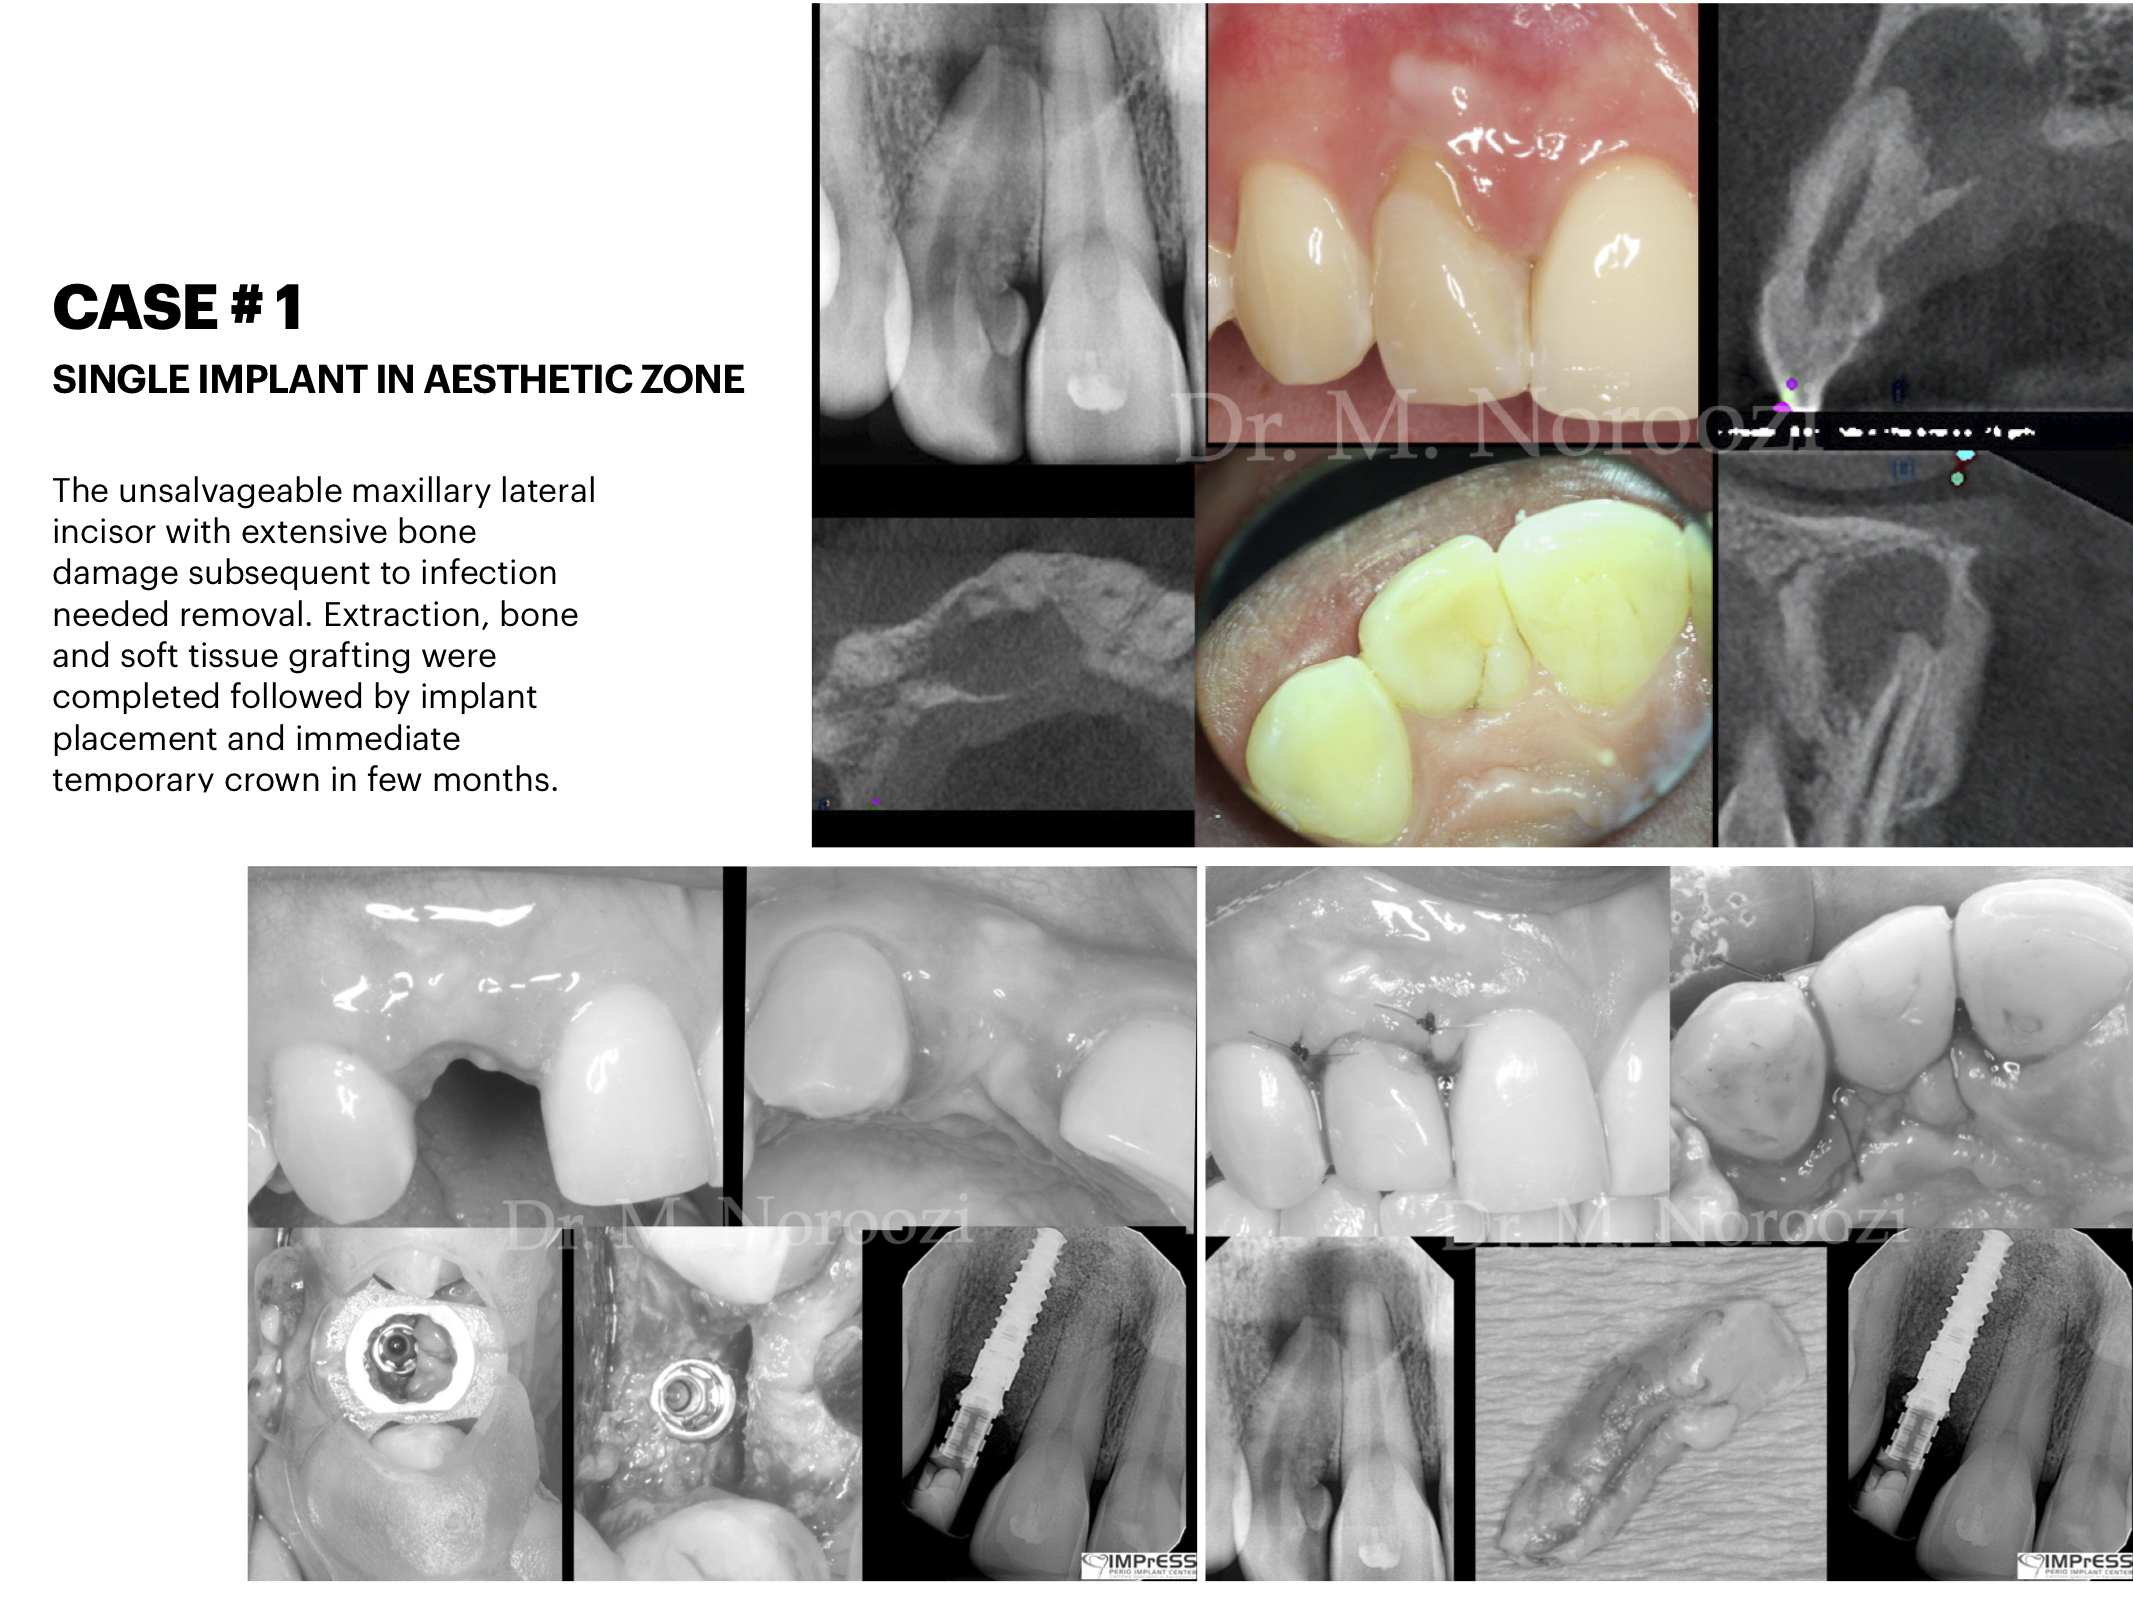

Front tooth implant Esthetic implant dentist Implant specialist IMPrESS Perio Implant Center Dr. M. Noroozi Implant Specialist